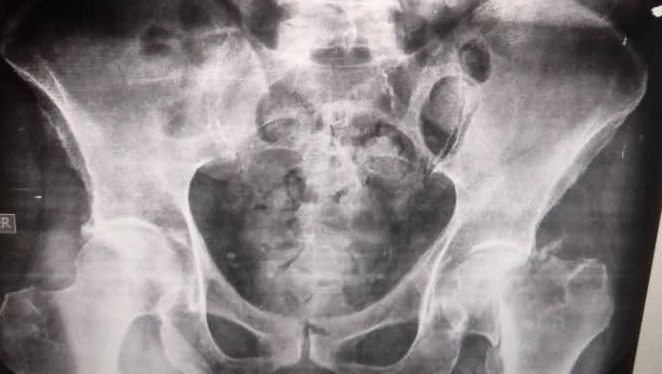

He recently lost balance and fell down on the floor, injuring his left leg. As you can see in the posted x-rays images below, as a result of this accident, he got a femoral neck fracture, which requires surgery to do a partial hip replacement, which includes a prosthetic femur neck and head (Thompson prothesis), besides miscellaneous medical bills and rehabilitation. The estimated cost of the whole procedure will go up to $10,000.